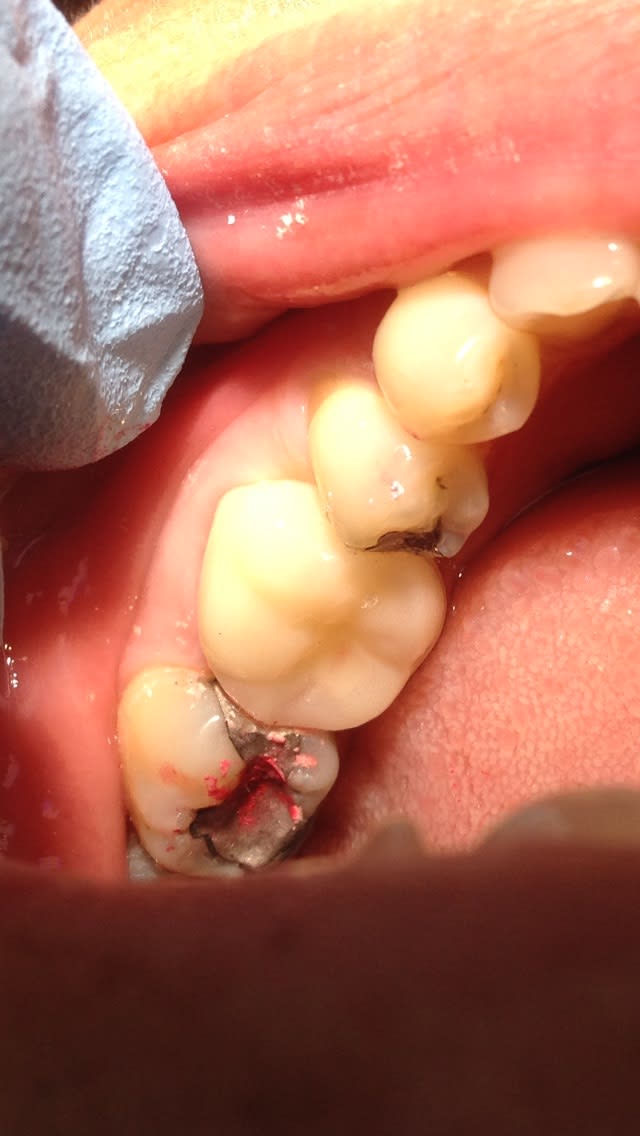

Regarde cette provisoire sur 36. On fait moins le malin là hein? 😊

La concavité sur l'amalgame de la 37 est de toute beauté.

Il y a quoi, qui descend derrière la CR métal (16?)???

Dit moi Enlaye, y manque pas la 37 et avec l'agression de 17 avec absence de 47, ben maman elle mange sur son rebord de cuvette, non ?

cette gonzesse a usé la glasure de ses bords libres de 2 façons:

- une usure chimique par le fluor du dentifrice ( il parait )

- et une usure par le frottement des levres , et ça ç est une erreur de strategie de ma part .

il lui manque une canine ( 13) ,elle etait en supraclusion ,hypodiv avec les incisives du bas en eventail , mais comak l'eventail .le tout associé à une perte de dvo ,bien sur , et toutes les dents mobiles

* et ,mon erreur est d'avoir commencé par le bloc ant du haut .

bien sur j'avais augmenté la dvo derriere par des compo mais pas assez .

cad ,que , ,comme je n'avais pas encore rentré les incisives du bas ,j'ai eté obligé de sortir les bords libres pour avoir la bonne longueur .

* à cela ,2eme erreur ,je n'ai pas vu l'interference post .

* 3eme erreur , les compos de calages temporaires se sont usés et elle est partie dans la nature .

du coup ,chaques fois qu'elle fermait , elle prenait appuis sur ces levres pour proteger ses dents de devant qui touchaient trop et aussi (ainsi) eviter l'interference post .